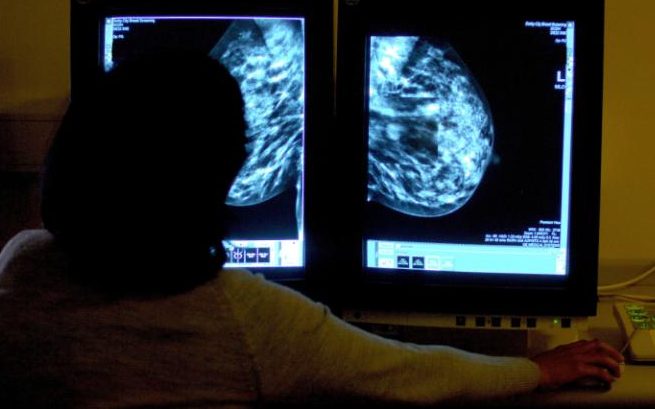

Các chi tiết vẫn còn ít trên thực tế, nhưng một trong những đội kế hoạch đang nghiên cứu máy học và thị giác máy tính - nơi mà máy tính thu thập thông tin từ các hình ảnh hoặc video, để cung cấp cho bác sĩ X - quang một sự hiểu biết tốt hơn về cách các khối u ở một bệnh nhân cụ thể tiến triển.

Bác sĩ X quang có kinh nghiệm có thể phát hiện những dấu hiệu tinh tế của bệnh ung thư vú ở những hình ảnh chụp quang tuyến vú chỉ trong nửa giây, một nghiên cứu cho biết. (Ảnh: PA)

Điều này có thể mở ra nhiều nhận định hơn về y học cá nhân.